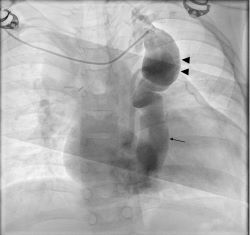

The preoperative angiogram did not show a left SVC although a rudimentary vein of Marshall was evident (Figure 2, Video 2). The mean PA pressure increased to 20 mmHg following balloon occlusion of the venovenous collateral, thus indicating it be a means to decompress the pulmonary circuit.